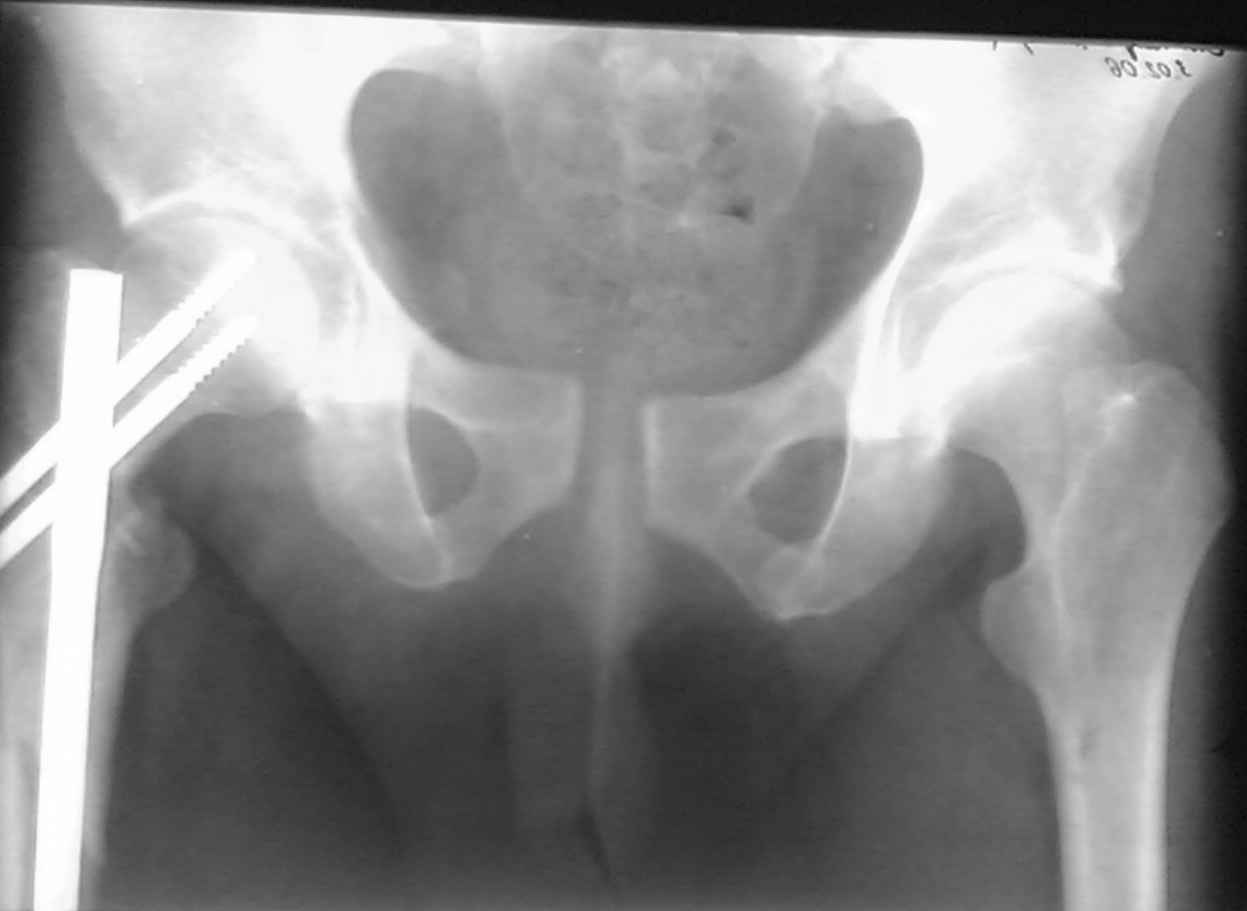

ПЕРЕСМАТРИВАЛ РАЗНЫЕ СНИМКИ И НАШЕЛ НА ЭТУ ТЕМУ ФОРУМА СНИМОК. БОЛЬНОЙ БЫЛ ПРООПЕРИРОВАН НА ПРАВОЕ БЕДРО ПОСЛЕ ЧЕГО СДЕЛАН ТАЗ В ЦЕЛОМ. ВОТ ЧТО НАШЛОСЬ.

КАКОЕ ВАШЕ МНЕНИЕ О ТАКТИКЕ.

ДУМАЮ ПРОШЛО ОКОЛО 10 ДНЕЙ.

В представленном случае повреждение несомненно ротационное и реальный диастаз как раз около пограничных 2,5 см, репозиция идеальная, достигнута в первые дни после травмы. Я бы ограничился 3 мес фиксации в аппарате с ограничением нагрузки первый месяц, и функциональными снимками в 6 -8 недель.

В представленном случае повреждение несомненно ротационное и реальный диастаз как раз около пограничных 2,5 см, репозиция идеальная,

достигнута в первые дни после травмы. Я бы ограничился 3 мес фиксации в

аппарате с ограничением нагрузки первый месяц, и функциональными снимками в 6 -8 недель.